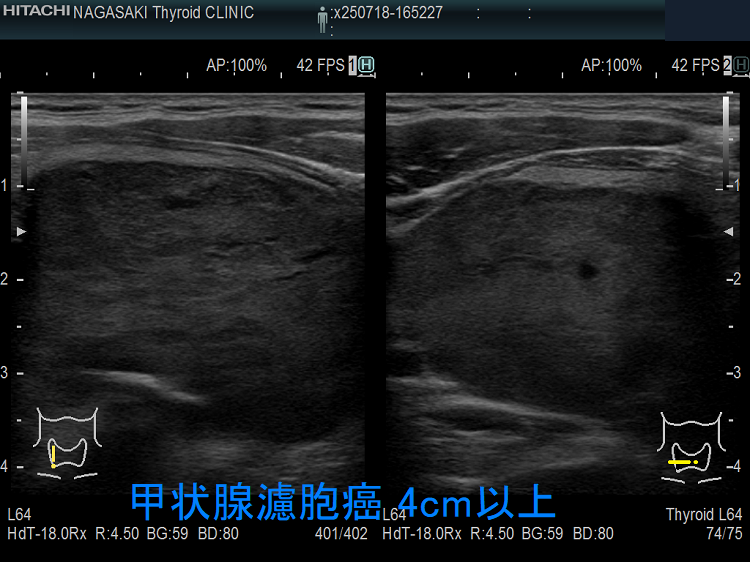

微小浸潤型濾胞癌でも巨大なものは、血管浸潤・遠隔転移します。写真のケースは 4cm以上の微小浸潤型濾胞癌で、切除標本にて血管浸潤を4カ所以上認め、Ki-67 labeling index 7% 高値(>5%)だった(エコーでは内部血流が少なかったのに)。

Ki-67 labeling index >5%は、増殖能が強く予後不良[World J Surg. 2010 Dec;34(12):3015-21.]。